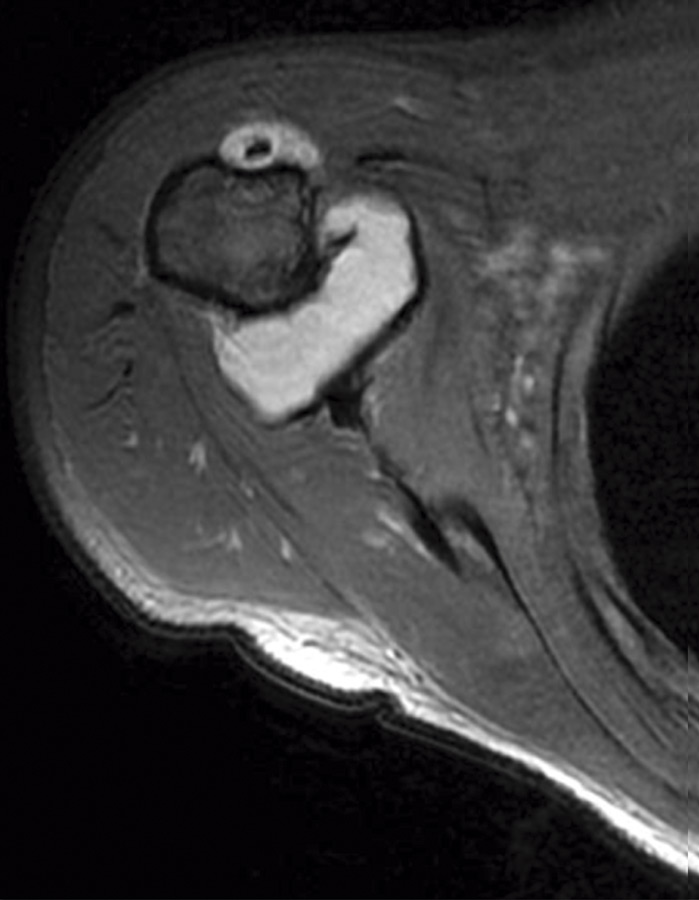

Se realizaron radiografías anteroposterior y axial de hombro, objetivándose calcificaciones intraarticulares, redondeadas, bien delimitadas. Ante dichos hallazgos, se procedió a la realización de una resonancia magnética (RM). En dicha prueba se objetivaron lesiones quísticas múltiples, bien delimitadas, algunas de ellas isointensas en T1, junto a otras lesiones hipointensas en T1 y T2 en la articulación glenohumeral compatibles con el diagnóstico de condromatosis sinovial (Figuras 1 y 2).

Figura 1. Resonancia magnética, T1 corte axial: condromatosis sinovial.